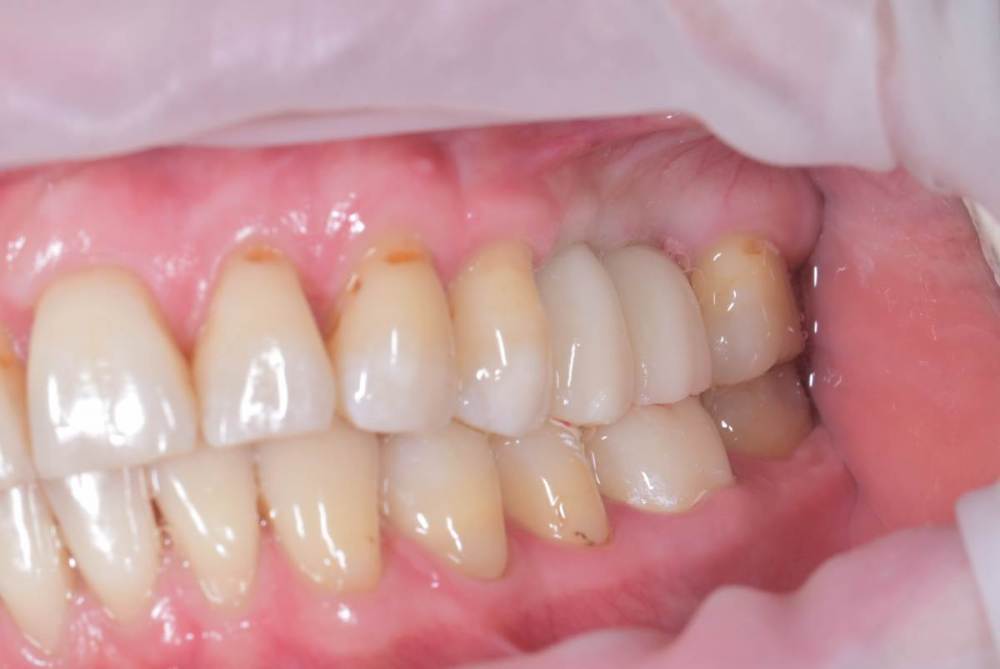

TIGER Опубликовано 8 мая, 2023 Автор Поделиться Опубликовано 8 мая, 2023 Всем привет!планировал удаление,но во время синуса решил использовать фрагмент как клин для стабилизации болта,в итоге совершил ошибку с более медиальной позицией 26,ибо шаблон не изготовил....через 5 мес одел времяхи,т.к будет тотал Ссылка на комментарий

Irouil Опубликовано 8 мая, 2023 Поделиться Опубликовано 8 мая, 2023 Вроде норм, в итоге 1 Ссылка на комментарий

TIGER Опубликовано 8 мая, 2023 Автор Поделиться Опубликовано 8 мая, 2023 @Irouil да,ортопедически всё отлично,я переживал Ссылка на комментарий